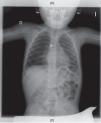

En la exploración física, la paciente presenta mal estado general, leve taquipnea e hipoventilación generalizada en el hemitórax derecho. En el análisis de sangre se aprecia una leucocitosis con neutrofilia. En la radiografía se valora una imagen radiopaca redondeada, compatible con una pila de botón impactada en el bronquio principal derecho y atrapamiento aéreo en el pulmón derecho (fig. 1).